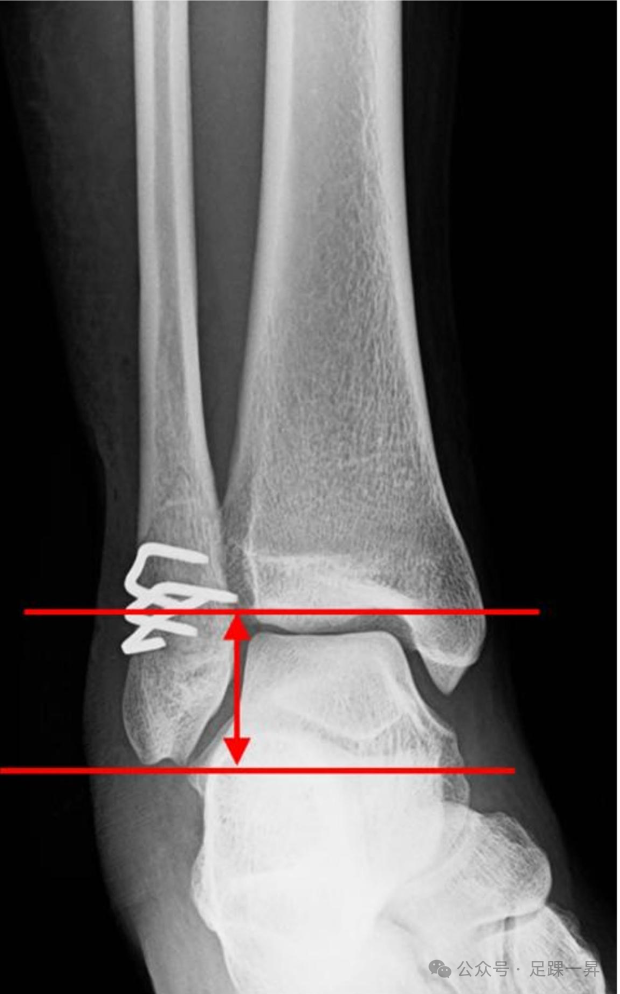

图示术后随访X线测量腓骨长度,腓骨长度为从腓骨尖端到胫骨关节面的距离,用于评估腓骨短缩情况。